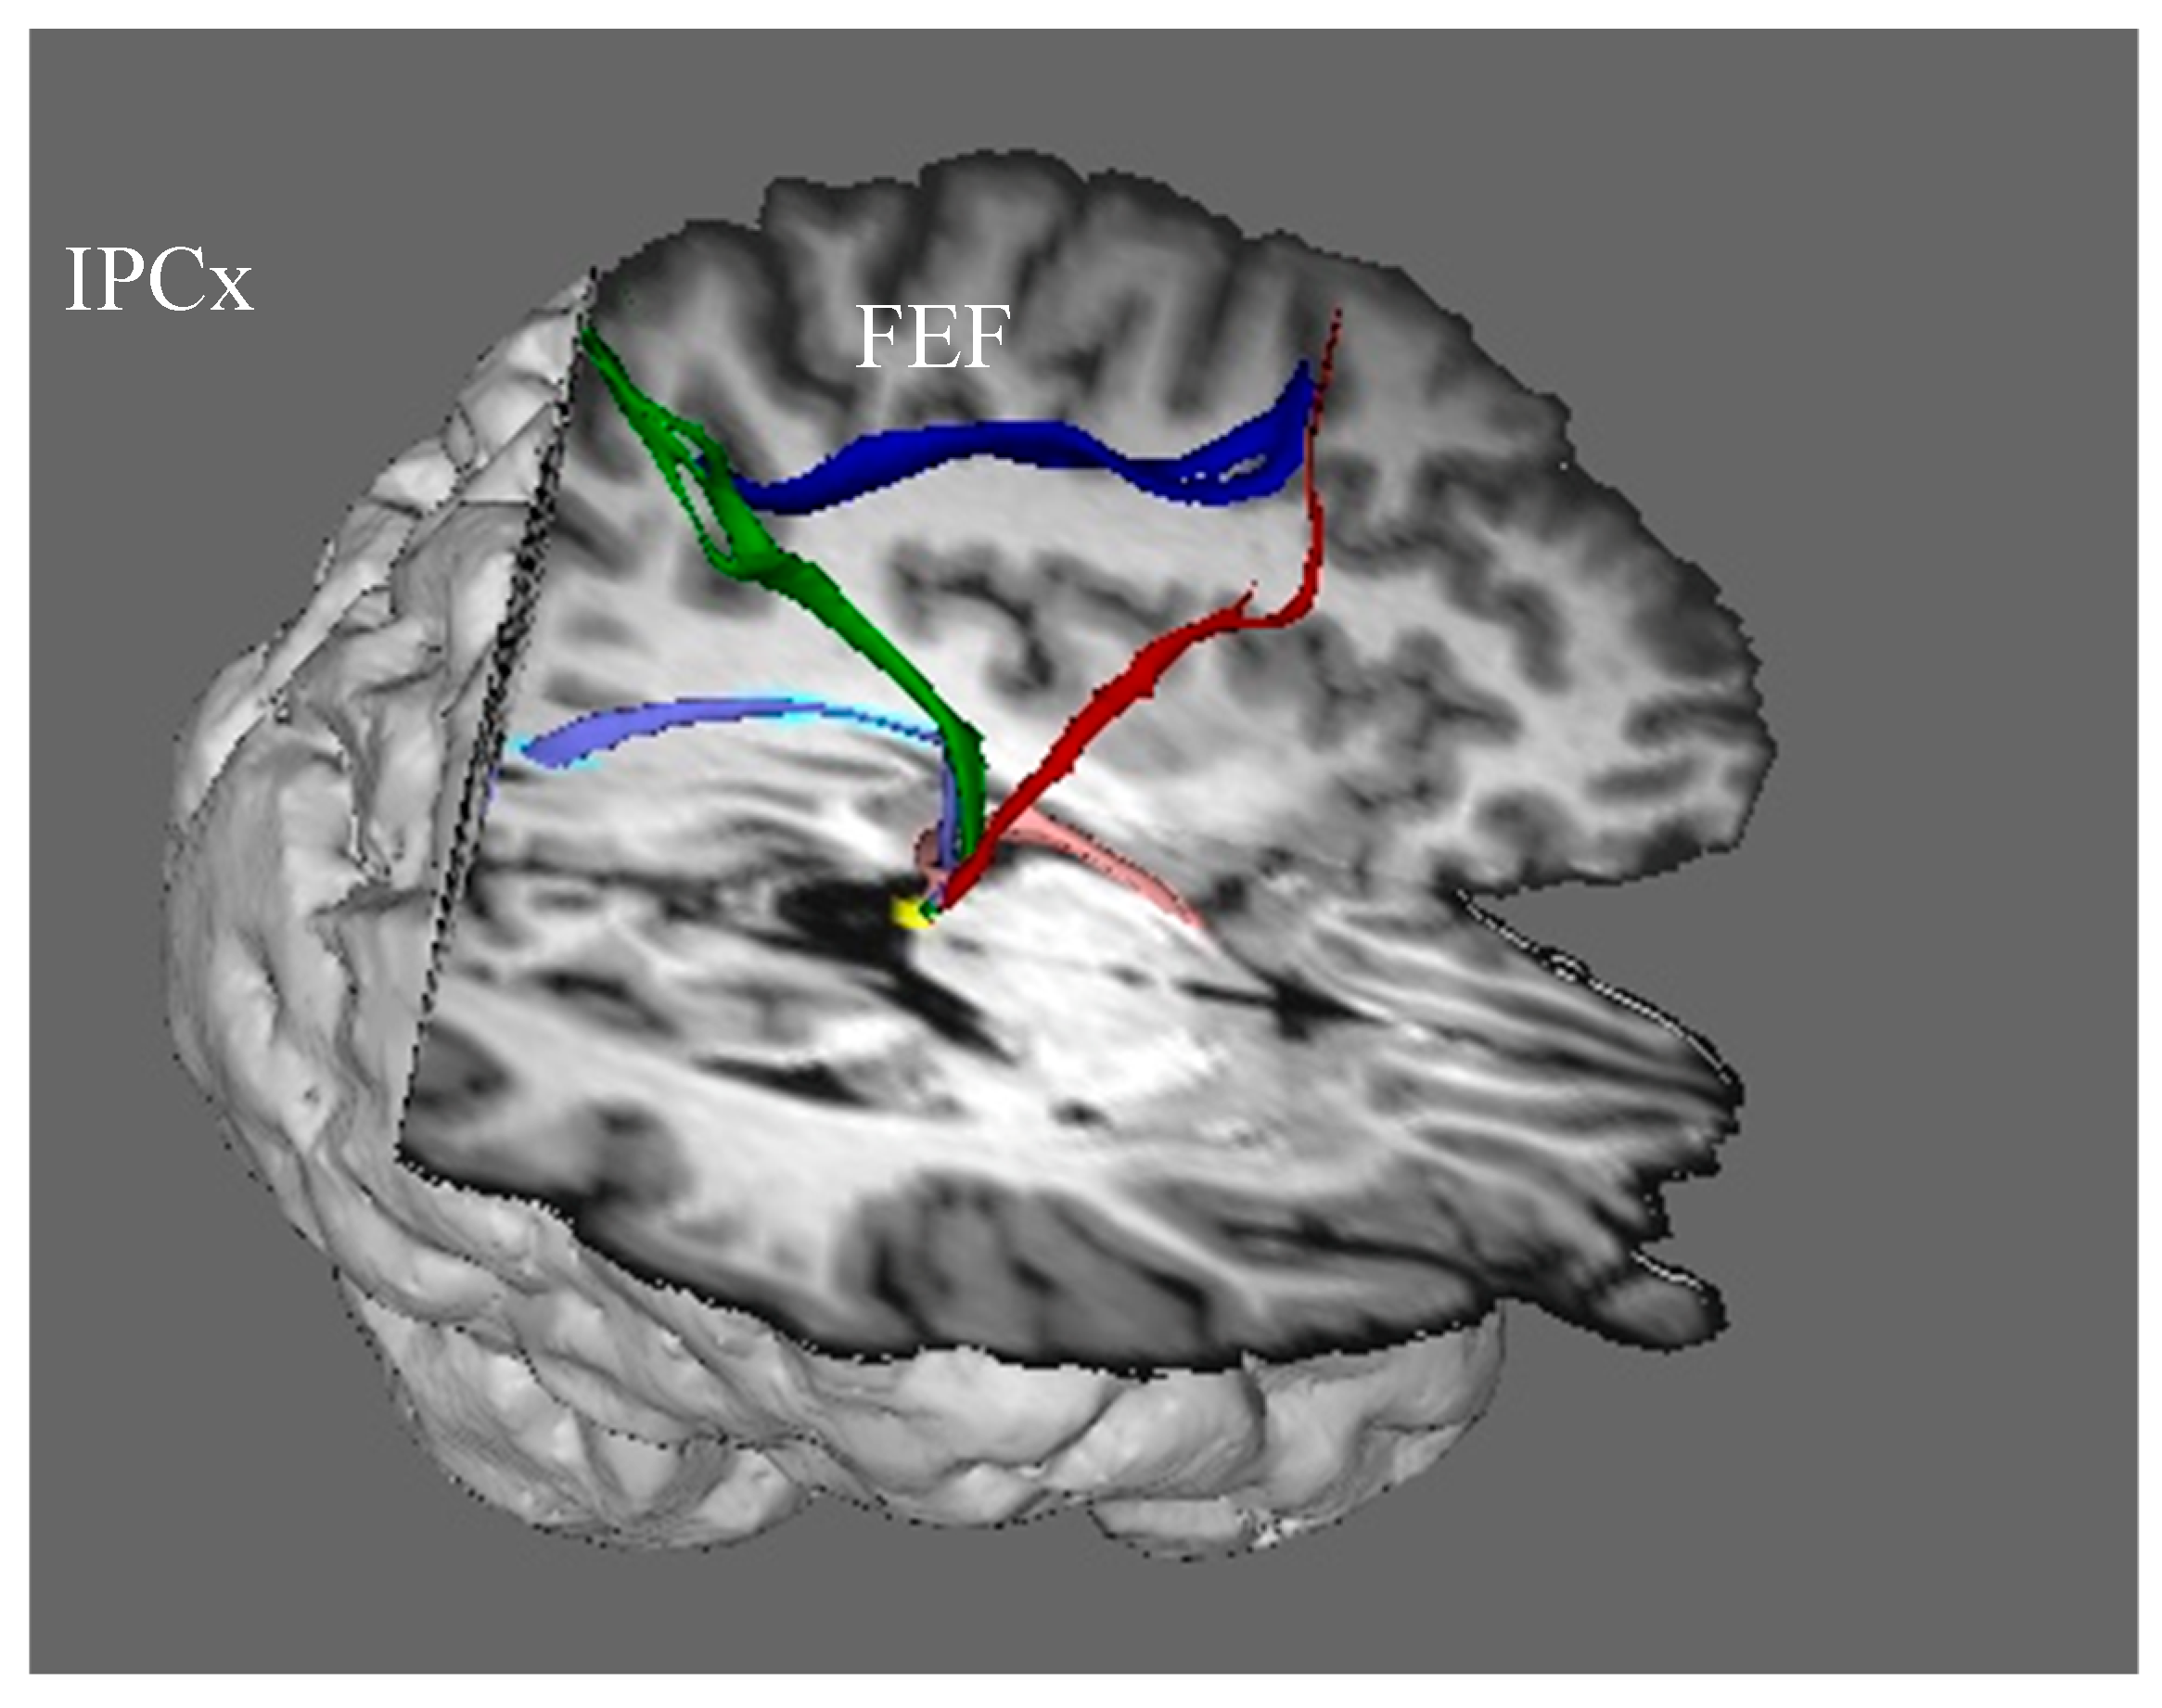

In addition to receiving visual input from the visual cortex, the intraparietal cortex also receives information from the superior colliculus about the position of the eyes in the orbits: when the superior colliculus sends eye movement commands to eye movement generators in the brain stem, a copy of the command is sent via recurrent axon collaterals to the intraparietal cortex via the frontal eye fields (the red streamline). The region of the frontal eye fields that receives eye movement signals from the colliculus projects information to the intraparietal cortex as a component of the superior longitudinal fasciculus (dark blue streamline), and the intraparietal cortex, in turn, projects it back to the superior colliculus (green streamline). The frontal eye fields also send commands for endogenously generated voluntary eye movements, directly and via the basal ganglia, to the superior colliculus, which is the final common pathway for initiating orienting responses.